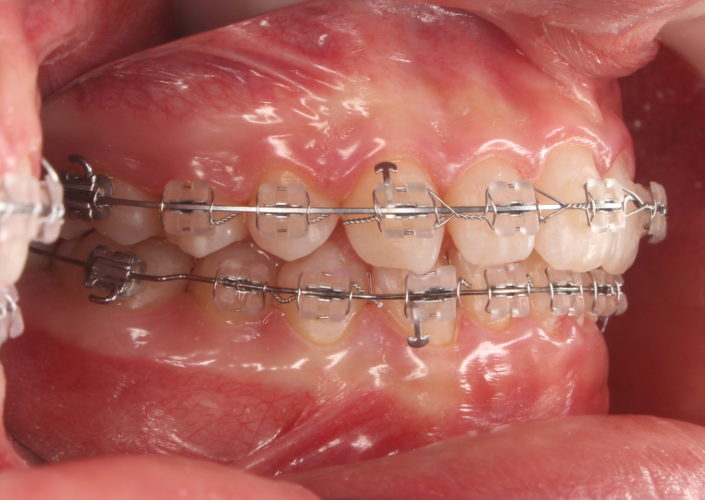

上下の装置が付いた状態です。

ミラー側方観(右側)

ミラー側方観(左側)

だいぶ上顎前歯が圧下され、下の前歯とのスペースが出来てきたので、矯正装置を装着しました。

ここから下顎前歯も圧下(下方に押し下げる)を開始し、歯軸(歯の傾き)等の改善も行っていきます。